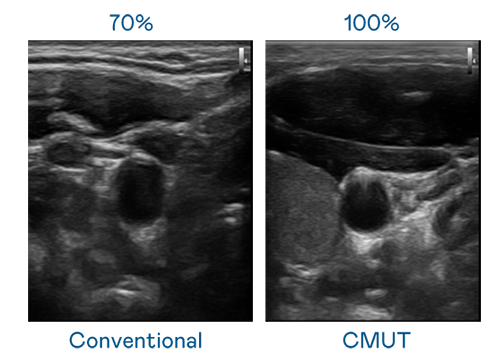

CMUT 技術是一種用電容式微機電元件來產生超音波訊號的技術。與傳統 PZT 壓電式技術相比,CMUT 頻寬增加 30%,更寬頻的超音波訊號讓影像解析度大幅提升,是實現高影像品質醫療超音波掃描、促進精準醫療發展的關鍵技術。

超音波影像的解析度高低,首先取決於探頭能發出的訊號頻寬。51cg.fun CMUT 可提供高清晰的超音波訊號,提供高頻寬、高靈敏度、影像紋理細節更高的超音波影像,協助醫護人員縮短影像判讀時間及利用精準的醫療影像進行診斷。